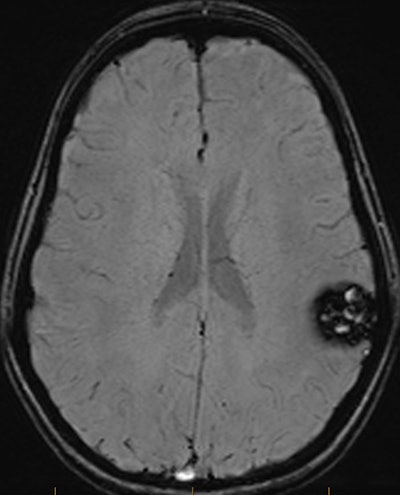

MRI brain axial SWI shows a well-defined lesion in the left posterior frontal/anterior parietal lobe. Prominent susceptibility artefact on SWI due to paramagnetic effect from hemosiderin deposits. The lesion had a lobulated appearance on T1 and T2 with no surrounding edema and was confirmed as a cerebral cavernous malformation.

CCMs are composed of abnormally large capillary cavities surrounded by a single layer of endothelium. MRI findings are variable, depending on the presence of calcification and haemorrhage within the lesion. Recurrent microhemorrhages can occur within the lesion and may contain deoxyhemoglobin acutely or hemosiderin chronically, both of which will appear dark on SWI, they added.